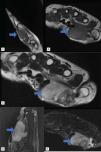

Plain radiographs (Fig. 1), ultrasound (Fig. 2), and magnetic resonance imaging (Fig. 3) were requested.

The ultrasound description of the GCTST is a hypoechoic, heterogeneous lesion, with Doppler, related to the affected tendon. On MRI it presents as a lobed lesion, of intensity in T1 and T2 which, in STIR, show intense enhancement. Determination of hypointense haemosiderin foci is useful in differentiating these from other lesions.